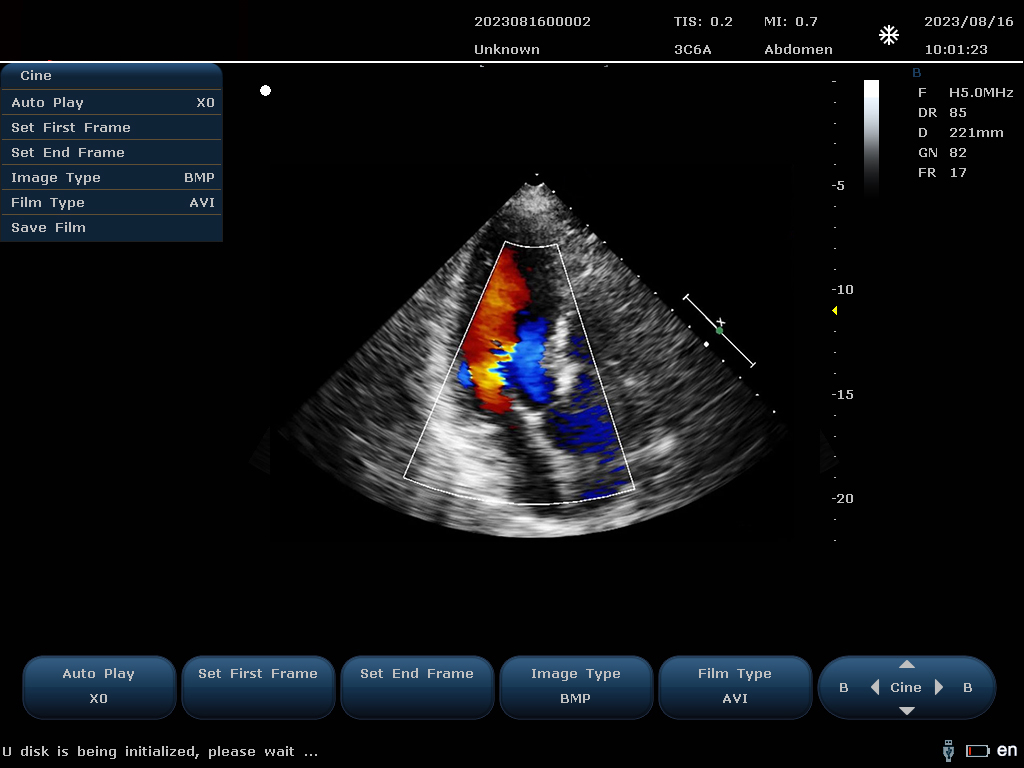

設(shè)備通過檢測(cè)這些頻移信號(hào),并利用復(fù)雜的信號(hào)處理技術(shù),包括傅立葉變換等,分析血流的方向、速度和分布。彩色編碼后,血流信息被疊加在傳統(tǒng)的黑白超聲二維圖像上,形成彩色多普勒?qǐng)D像,直觀顯示血流動(dòng)態(tài)。

最終,這些信息轉(zhuǎn)化為圖像顯示在屏幕上,醫(yī)生可以根據(jù)圖像中血流的顏色(通常紅色代表血流朝向探頭,藍(lán)色代表遠(yuǎn)離探頭)和亮度來(lái)判斷血流的性質(zhì)和異常情況,如血流速度增快可能指示狹窄,無(wú)血流區(qū)域可能意味著阻塞等。